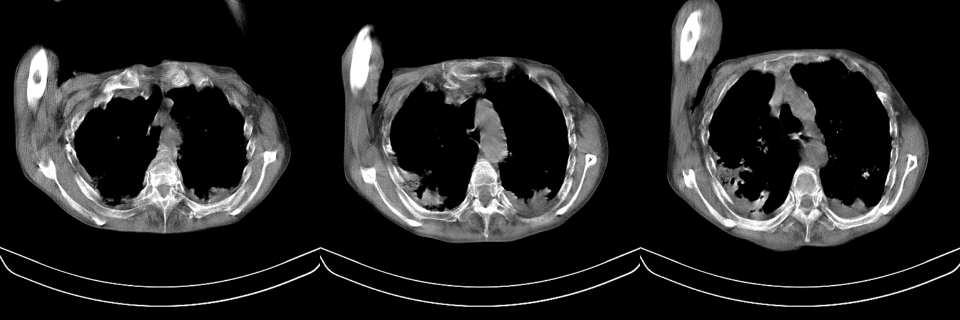

以下是引用mzh123在2007-8-26 19:58:00的发言:[br]两肺弥漫性斑片改变,其中可见大小不等之不规则空洞,结合既往病史还是考虑结核复发及感染。

以下是引用云翔在2007-8-26 20:54:00的发言:[br]这是44岁的肺吗?是否有先天病的基础?干酪性肺炎?